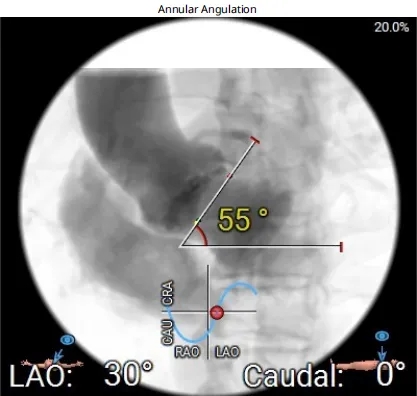

type1型二叶瓣,左右融合,融合嵴见钙化,无冠瓣钙化重,环上结构空间可。左右冠脉开口高度可,结合左右融合,冠脉风险低。瓣环夹角约55°,偏横位心,右无交界无严重钙化融合,系统通过顺畅,同轴性欠佳。收缩期左室内径约29*38mm,舒张期瓣叶疑似关闭良好,反流轻,无冠瓣钙化重。室间隔膜部环下长度约3.4mm,流出道较宽约28.1mm,传导阻滞风险低。双侧入路内径可,股动脉分叉皆在股骨头下缘,未见弓部CT影像,升主无明显扩张。

70男性患者,type1型二叶瓣,主动脉瓣重度狭窄,无冠瓣钙化重,瓣环平均直径27.2mm,LVOT平均直径27.6mm,右冠脉开口高度可,冠脉风险低,瓣环夹角约55°,偏横位心,外周血管入路条件可。经手术团队综合评估后,拟在纯超声引导下以右侧股动脉为主入路行经导管TAVR,术中选择22mm球囊预扩,拟植入29# Evolut PRO瓣膜,初始释放3节瓣架后定位无窦0位,最终控制植入深度3-5mm,根据情况选择是否后扩。手术在中国科学院阜外医院潘湘斌院长团队指导下完成。